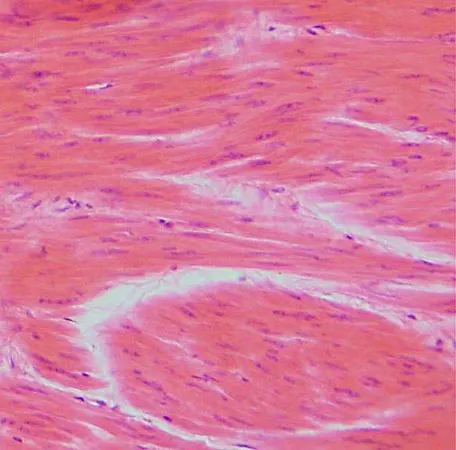

cardiac muscle

knowt flashcard image